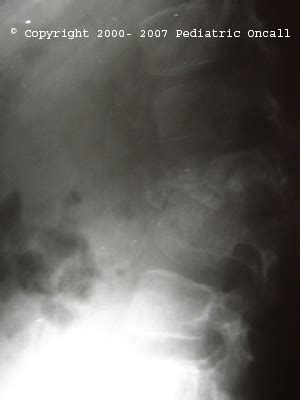

Vertebral Collapse Or Compression Fracture Of Vertebra | Spot Diagnosis ...

Rul Collapse

Radiology Rul Collapse

Right Upper Lobe Collapse

Collapsed Lobe Rul

X-ray Rul Collapse

Rul Collapse Radiography

Lobar Collapse